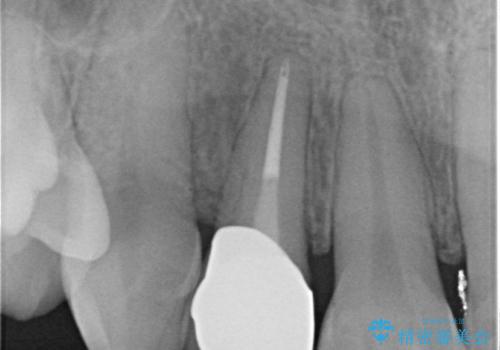

- 右上前歯の形と色が気になるとのことで来院された患者様です。

残っている歯に亀裂が多く走っていたため、クラウンでの修復処置を行います。

- 右上2 仮歯/11,000円 ファイバーコア/22,000円 ジルコニアクラウン(スタンダード)/121,000円 合計154,000円費用は治療当時の料金となります

歯ぐきの扱いに気を付けることで、術前よりも歯ぐきの位置が改善されました。